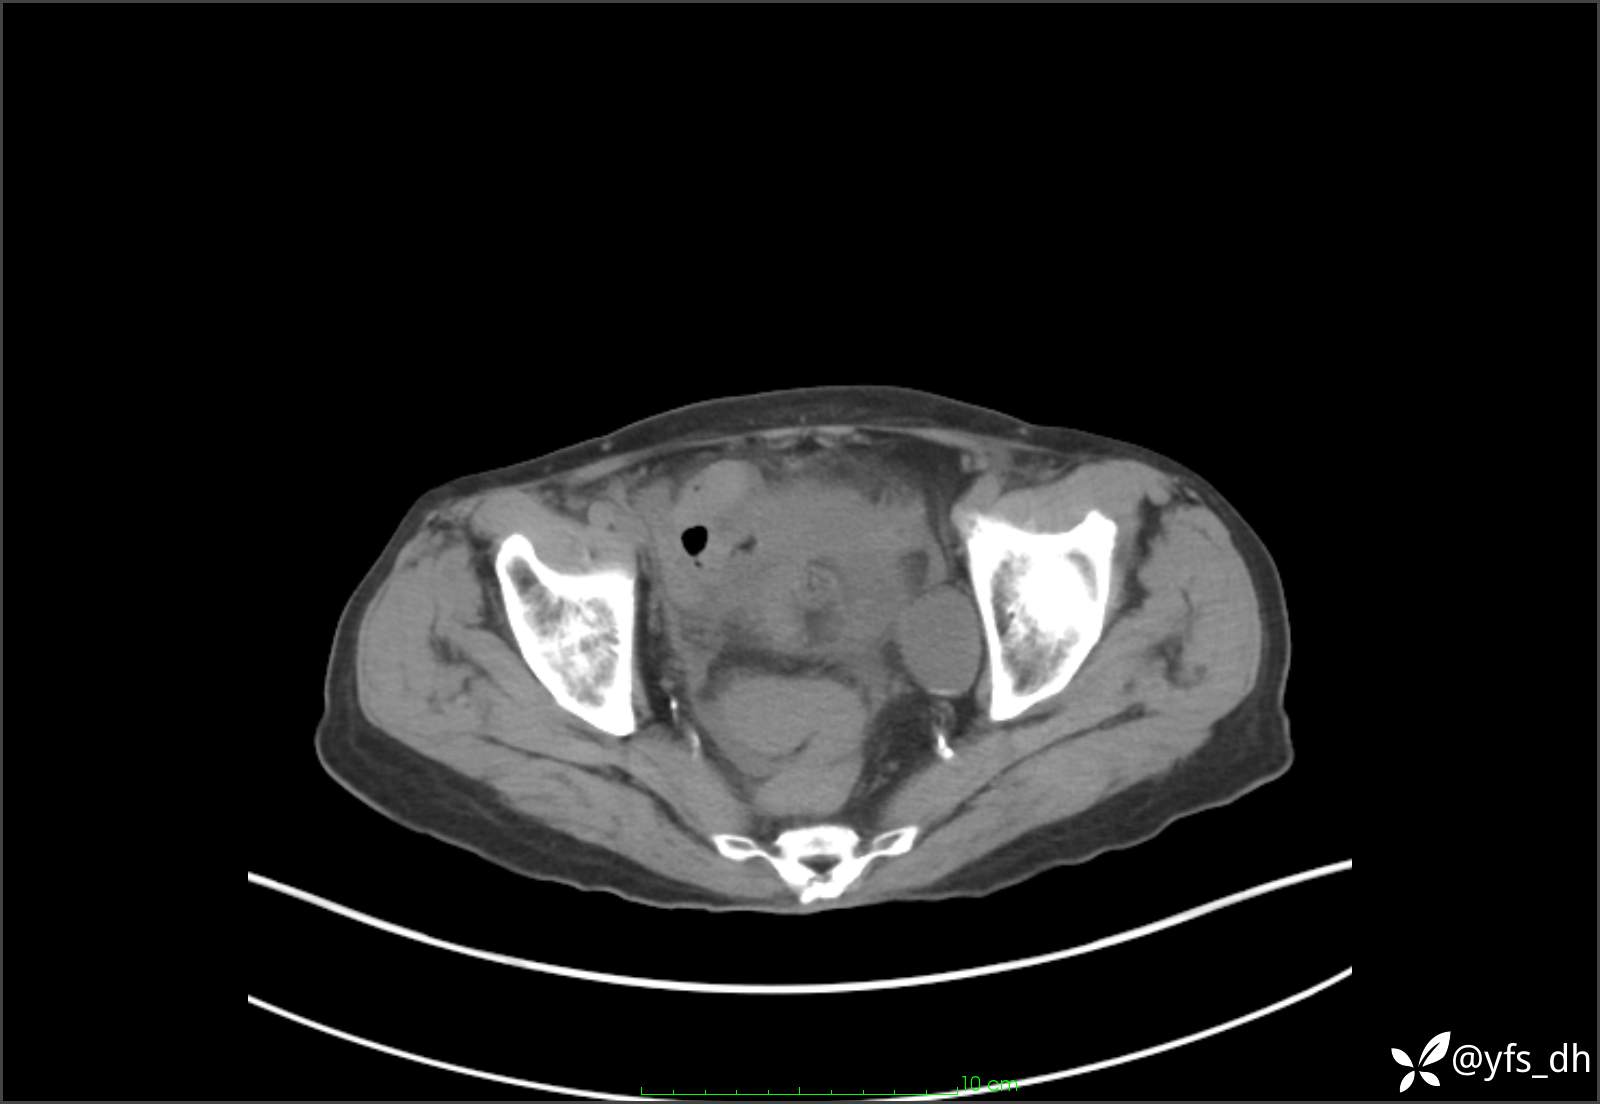

1.简要病史:患者4天前突发上腹部疼痛不适,但可以忍受。3小时前饭后突然加重,不能忍受后就诊。

2.简要手术记录:术中见腹盆腔大量肠液及粪便,乙状结肠中下段见一约3cm的破口。